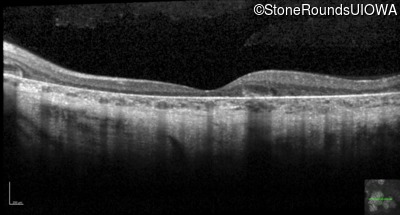

Optical Coherence Tomography - Left - 20/30 +1 sc

Exemplar / OCT Stack